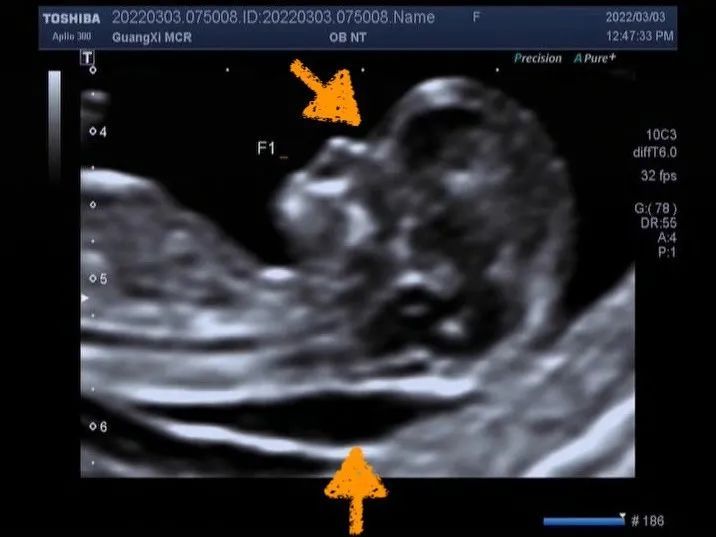

1. 早孕期常见的超声异常:颈项透明层(NT)增厚、鼻骨缺失。